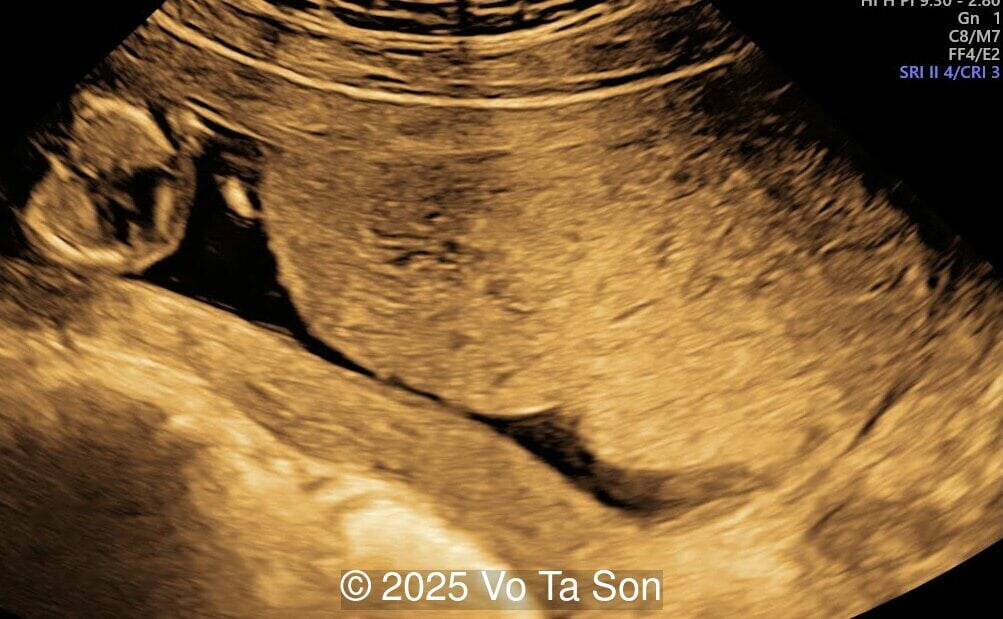

A 13-week pregnant woman underwent routine prenatal screening. The non-invasive prenatal test (NIPT) showed low risk for common aneuploidies (trisomy 21, 18, and 13). However, first-trimester anomaly scan revealed the following significant fetal abnormalities:

- Open spina bifida in the sacral region with dry brain and crash sign, BS/BSOB >1, direct lesion at sacral coccygeal spine